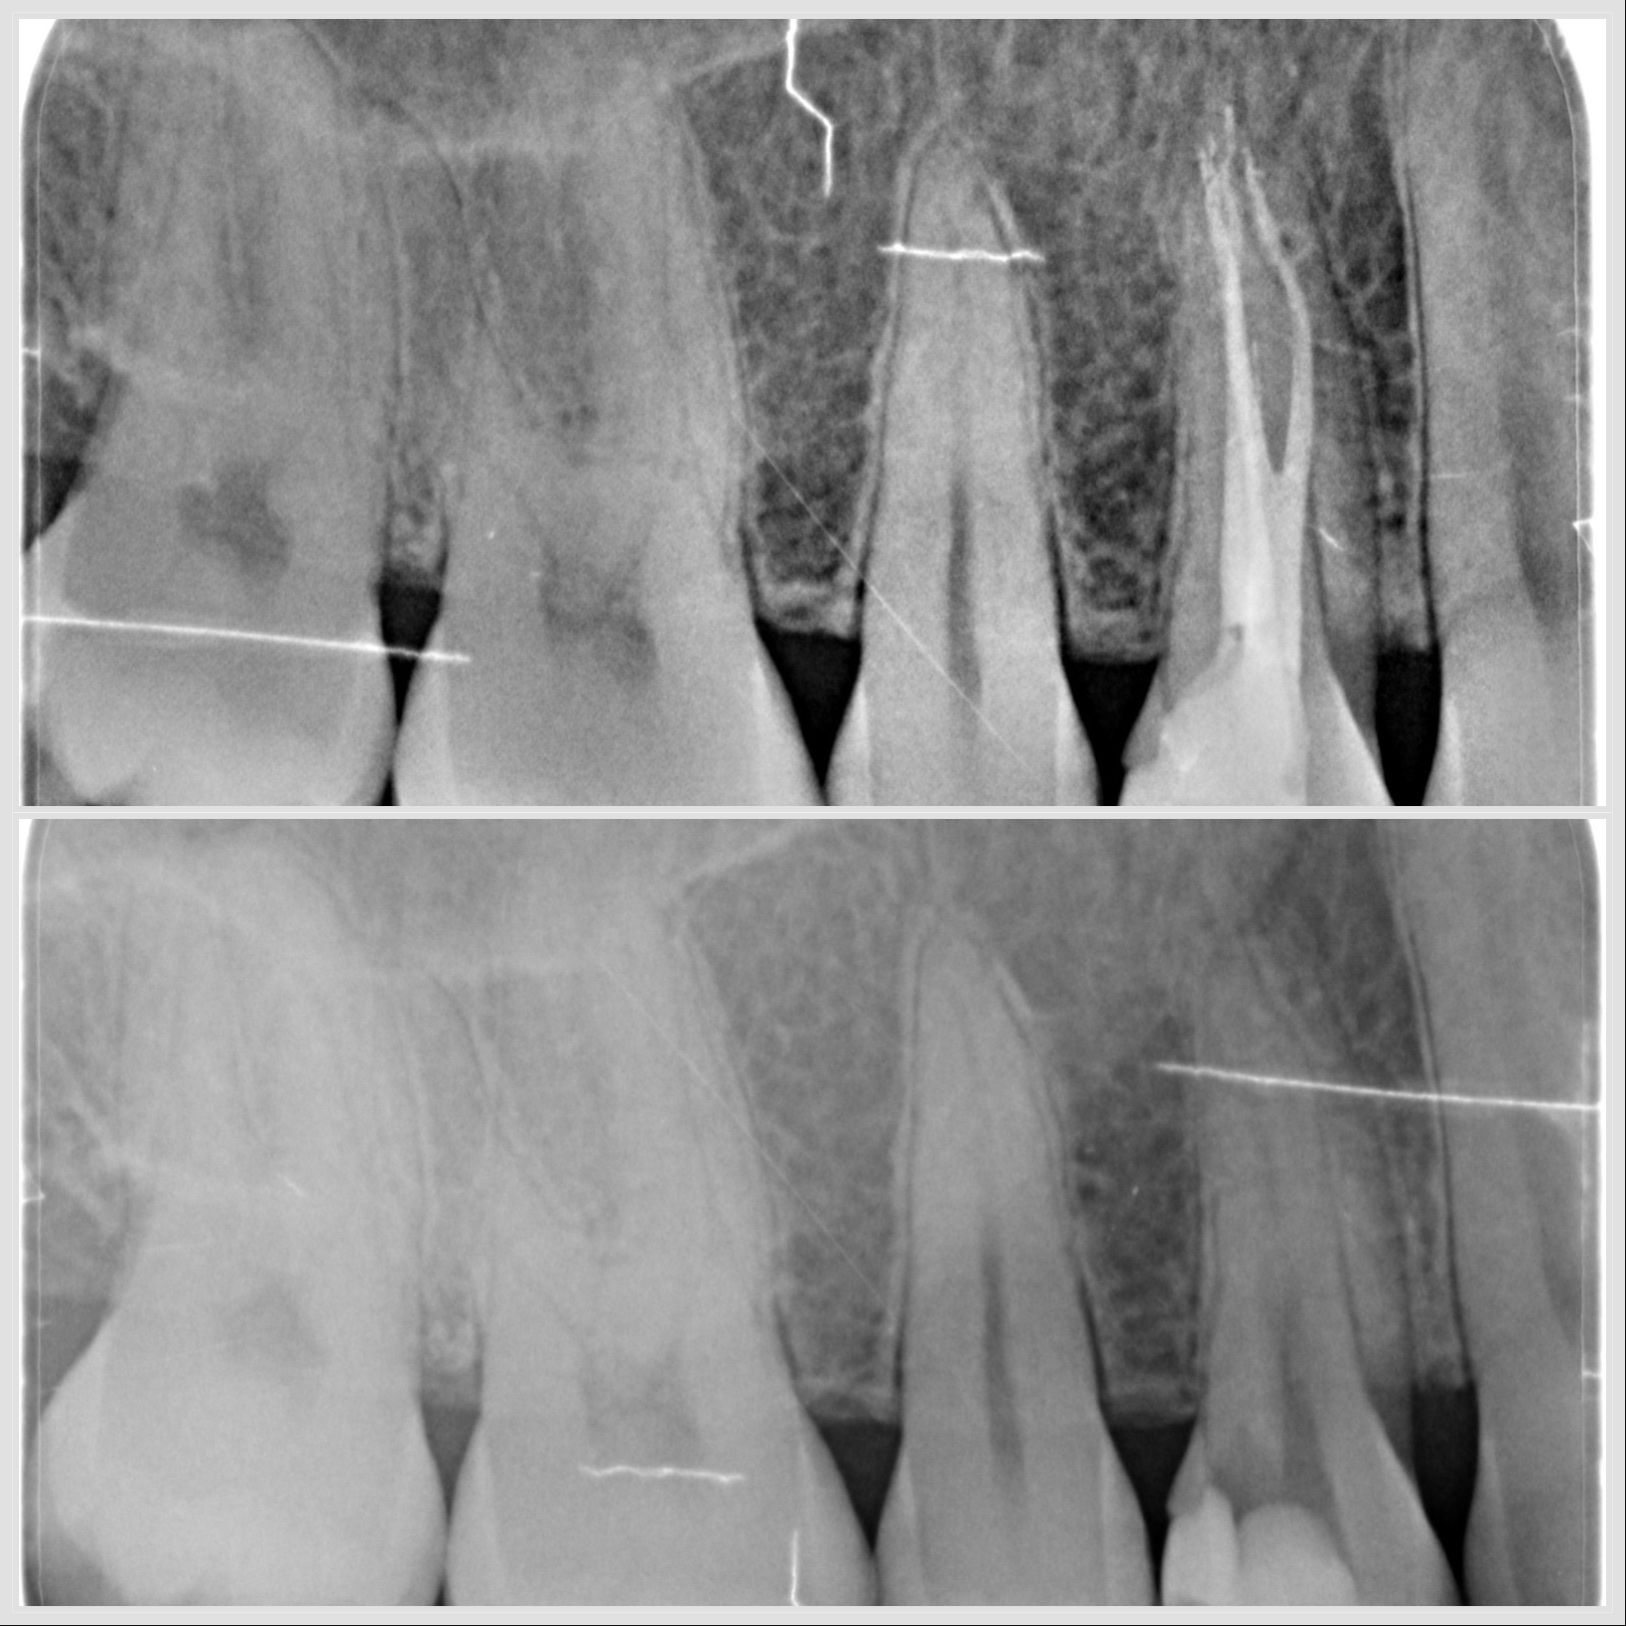

Prémolaire mandibulaire avec trois canaux traitée sous microscope à Apolline Dental Care à Corbeil-Essonnes

Endodontie prémolaire 3 canaux

Lésion endo-parodontale sur molaire mandibulaire traitée en endodontie et parodontologie à Apolline Dental Care à Corbeil-Essonnes

Lésion endo-parodontale

Traitement endodontique sur prémolaire avec trois canaux réalisé à Apolline Dental Care à Corbeil-Essonnes

Endodontie sur prémolaire à 3 canaux